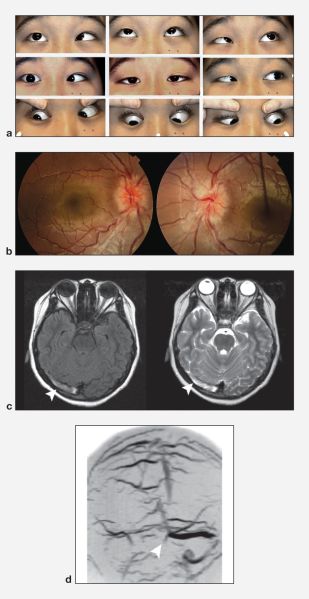

Venous sinus thrombosis. A 14-year-old boy presented with a 2‑week-history of headache, double vision, nausea, and vomiting due to venous sinus thrombosis. A, Nine positions of gaze demonstrating bilateral CN VI paresis. B, Funduscopy shows bilateral optic disc edema. c. T1‑weighted (left) and T2‑weighted (right) MRI shows thrombosis in the right transverse sinus (arrows). d. Magnetic resonance venography demonstrates no filling of the right transverse sinus (arrow). American Academy of Ophthalmology. https://www.aao.org/education/image/venous-sinus-thrombosis-2 Accessed December 20, 2024.